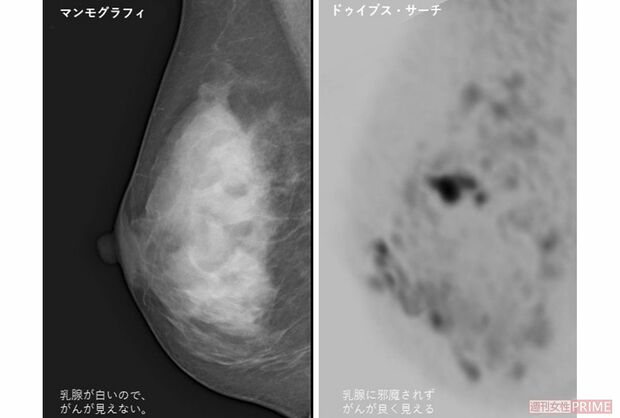

左はマンモグラフィーで撮影した高濃度乳房。白っぽく写りわかりにくいが、右のドゥイブス・サーチでは腫瘍がよく見える※画像提供・高原医師

[写真 2/2枚目] 左はマンモグラフィーで撮影した高濃度乳房。白っぽく写りわかりにくいが、右のドゥイブス・サーチでは腫瘍がよく見える※画像提供・高原医師